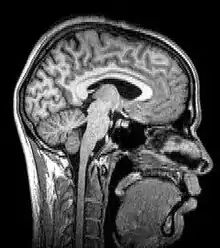

Para-sagittal MRI of the head in a patient with benign familial macrocephaly

Sagittal MRI slice at the midline

Magnetic resonance imaging (MRI) uses magnetic fields and radio waves to produce high quality two- or three-dimensional images of brain structures without the use of ionizing radiation (X-rays) or radioactive tracers.